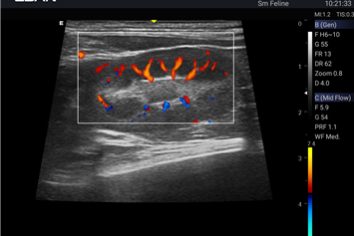

Tissue Adaptive Imaging (TAI) continuously and automatically optimizes imaging

Dual transducers design can simplify workflow and improve the diagnostic efficiency